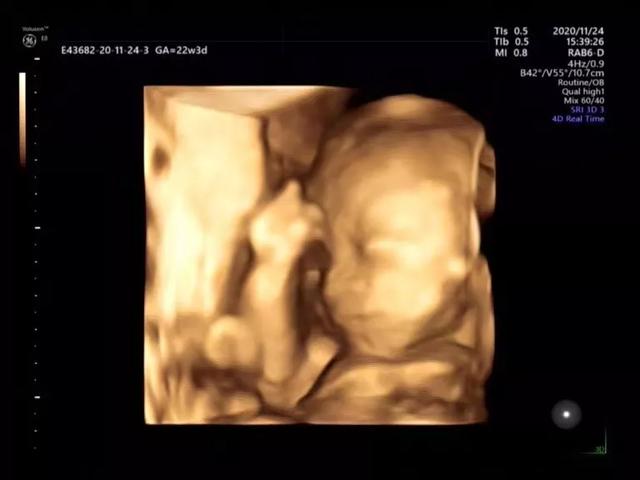

如果宝宝配合,还可以拍一张可爱的四维照片。